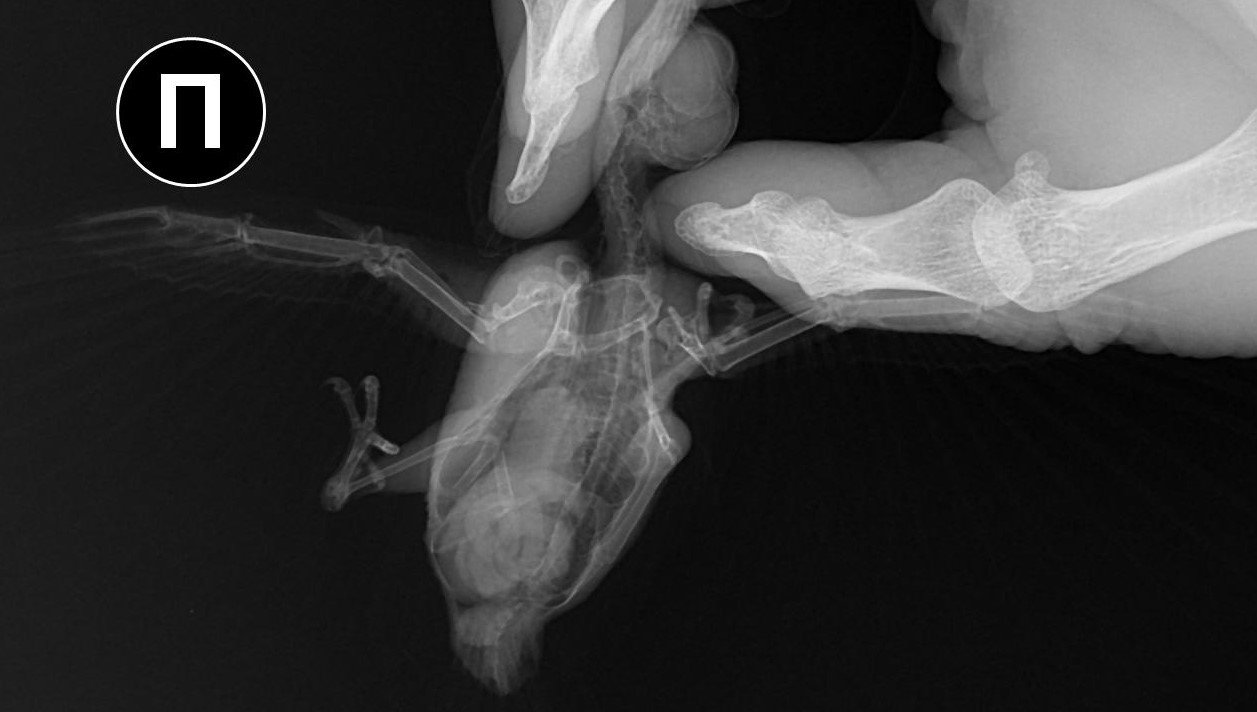

Добрый день. Три дня назад подобрал на улице птицу с неестественным положением правого крыла (о том, что это стриж узнал от ветеринарного врача). Занес в ближайшую ветеринарную клинику, где врач, осмотрев и ощупав птицу (рентгена в клинике не было), сказал, что перелома нет, скорее всего стриж ударился о провод и ему необходимо несколько дней для восстановления. Никогда не имел дел не только со стрижами, но и с птицами вообще, но решил попробовать его спасти. Живет в коробке примерно 30х30х30, кормлю опарышами, так как пока не нашел других насекомых, этот вопрос решу в ближайшее время. Вопрос с питанием отдельная проблема. Больше всего меня беспокоит его крыло. Сегодня свозил птичку на рентген. Врач хотя и увидел перелом, но о лечении птиц знает примерно столько же сколько и я. Даже не знал, как называется сломанная кость (называл её маленькой) Я потом посмотрел в интернете, что это лучевая кость. А локтевую кость называл маховой. Предложил зафиксировать крыло и, прижав крылья к телу, замотал его эластичным бинтом. Приехав домой, я снял эту повязку. Не знаю смогу ли найти ветеринара по птицам, а пока прошу совета и помощи у знающих людей. Есть ли шанс вылечить птицу с таким переломом? Нужно ли её пеленать, как сделал этот врач? Может быть поместить стрижа в маленькую коробочку, чтобы у него не было возможности махать сломанным крылом? В общем, что сейчас делать с птичкой? Спасибо за советы PS На последнем снимке стрижик завернут в эластичный бинт